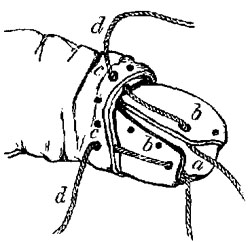

Ligature above Omohyoid.—Using the anterior border of the sterno-mastoid as a guide, but leaving it gradually above to a little nearer the mesial line, an incision (Plate IV. fig. 1), varying in length according to the depth of fat and cellular tissue in the neck, but with its central point opposite the upper border of the cricoid cartilage, must be made through skin, platysma, and superficial fascia. While making the incision the head should be held back, and the face slightly turned to the opposite side; the parts being now relaxed by position, the edges of the wound must be held apart by blunt hooks or copper spatulæ, and the deep fascia carefully divided over the vessel, which will be recognised by the pulsation. It may be noted here that even in thin subjects the sterno-mastoid edge invariably overlaps the vessel, though in many anatomical diagrams it would appear to be in part subcutaneous.

The sheath of the vessel is then to be cautiously opened to the extent of about half an inch. The internal jugular vein, possibly much distended, may overlap the artery on its outer side, and will require to be pressed, emptied, and held out of the way. A small portion of the artery being thoroughly separated from the sheath, the aneurism-needle must be passed from without inwards to avoid the vein, and keep as close to the artery as possible to avoid the vagus.

Ligature of Carotid below the Omohyoid.—An incision in precisely the same direction as the former, but at a slightly lower level, is required, but the dissection is rather more difficult. The edge of the sterno-mastoid when exposed must be drawn outwards; the sterno-hyoid and thyroid inwards; the omohyoid upwards; the sheath opened, and the descendens noni or its branches drawn to the tracheal side. The jugular vein and vagus are both at the outer side, and must be avoided, while the inferior thyroid artery and sympathetic nerve both lie behind the vessel, and may be included in the ligature if care be not taken.

Varieties.—Sedillot's Operation.—To secure the artery still lower in the neck: An incision two and a half inches long, from the inner end of the clavicle obliquely upwards and outwards in the interval between the sternal and clavicular attachments of the sterno-mastoid; this divides the superficial textures; the two portions of muscle must then be drawn apart. The internal jugular vein lies in the interval, and must be drawn to the outside before the artery can be seen at all, and it is this that makes this operation very difficult and dangerous, especially on the left side, where the vein is close to the artery, and probably even crossing it from left to right. The thoracic duct is behind.

Malgaigne's modification of the above is an improvement: to expose the external attachment of the muscle, to cut it through and turn it to the outside, as in the operation for ligature of the innominate, then to divide or pull inwards sterno-hyoid and sterno-thyroid, thus exposing the sheath. The needle must be passed from without inwards.